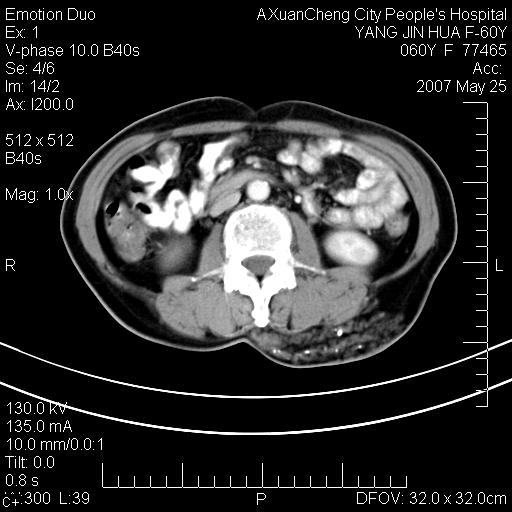

发现左侧腰背部包块40余年,逐渐长大,质软,局部表面可见扩张的血管影

左背部皮下良性肿瘤,密度不均,边界不清,内有脂肪、钙化,增强扫描无明显强化,血管平滑肌脂肪瘤?进一步诊断有困难,建议穿刺活检。

左侧背部皮下混杂密度肿块,结构较疏松,边缘欠光整,内有多发斑点状钙化,考虑:皮下血管瘤。

其内可见斑点状静脉石,血管瘤有时就不增强化,还是血管瘤。

1、病灶内有小点状钙化,静脉石?这可是血管瘤诊断的重要征象

2、病灶内有脂肪组织增生,血管瘤有此特点